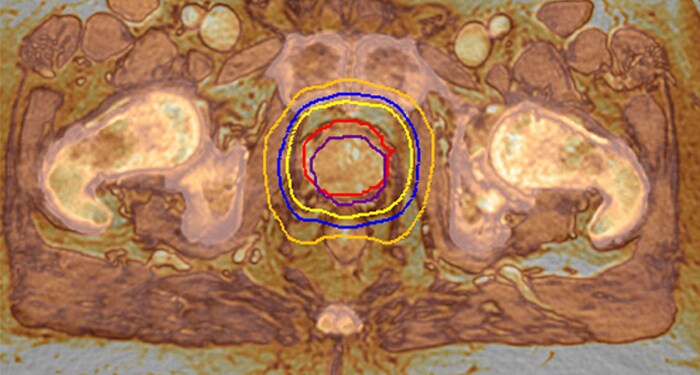

MR-RT XD meets the need for accuracy with advances in image quality, geometric fidelity, and reproducible patient positioning. You acquire high quality MR images in the treatment position, boosting accuracy in target delineation and critical structures.

Highly targeted treatment plans rely on MR imaging performed in the treatment position. With MR-RT XD you acquire high quality MR images in the treatment position, boosting accuracy in target delineation and critical structures.

MRCAT lets you plan radiation therapy based on one MR exam. By excluding the need for CT, this helps relieve the burden on your clinical resources, reimbursement obligations and budget. And your patient is spared to undergo a second scan – reducing the patient burden.